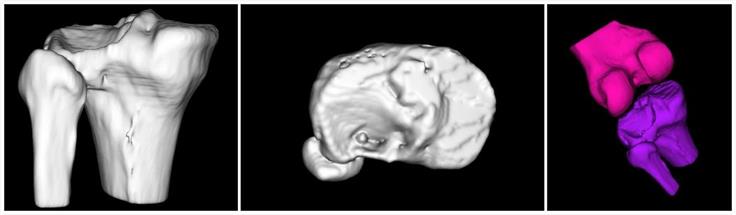

- 模擬病人骨折,讓醫(yī)生更直觀的了解骨折情況

- 軟件模擬手術入路,為醫(yī)生選擇最佳入路提供參考

該手術在軟件的輔助下確定以不剔除腓骨的方式進行手術